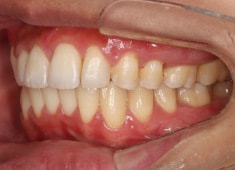

治療前

治療開始時